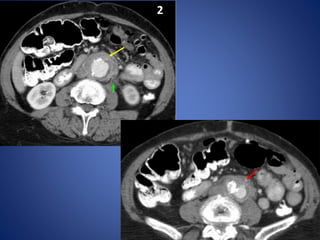

Retroperitoneal Fibrosis

There is a thick rind of soft tissue surrounding the aorta from the level of the kidneys (top photo-

yellow arrow) to and including the bifurcation (bottom photo-red arrow).

Notice the aorta is not displaced forward as it would more likely be in lymphoma.

Retroperitoneal fibrosis (RPF) is a condition that has previously been described as

chronic periaortitis.

It is an uncommon fibrotic reaction in the retroperitoneum that typically presents

with ureteral obstruction.

On excretory or CT urography

§ Most retroperitoneal masses displace ureters laterally

§ Tapering of ureters distal to mass

On CT scans

§ Rind of soft tissue around aorta and inferior vena cava between level of

kidney and sacrum

§ Spreads to involve the ureters, causing varying degrees of obstruction.

§ Fat plane between the mass and the psoas muscle may be obliterated

§ Unlike adenopathy, RPF tends not to displace aorta anteriorly

§ Mass may show varying degrees of enhancement depending on the stage of

the disease